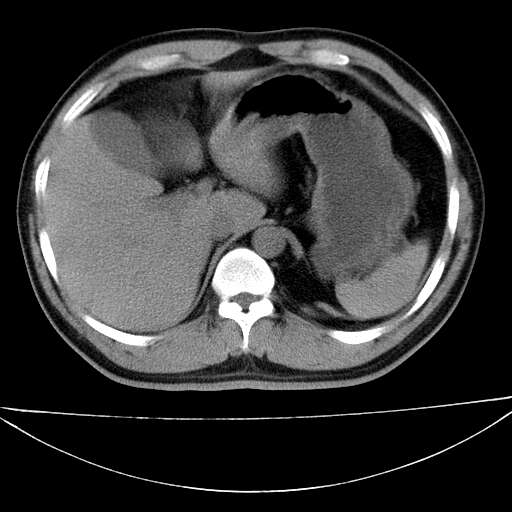

标题: CT21921:腹膜后腔肿物。患者男39Y。体检。增强扫描时间欠准 [打印本页]

标题: CT21921:腹膜后腔肿物。患者男39Y。体检。增强扫描时间欠准

左侧膈肌脚外缘见一结节样软组织影,密度较均匀,与胸膜关系稍密切,增强轻度强化;考虑来自胸膜良性病变(胸膜纤维瘤可能)。建议加扫胸部ct检查。

2、左下膈肌脚外缘结节状病变,与胸膜交界面呈锐角,胸膜下脂肪线可见,定位于肺内,考虑支气管囊肿或肺隔离征可能性大。

膈疝

1)考虑左肺下叶后基底段(或左下胸后壁胸膜)软组织团块,性质待定;建议行进一步检查。2)左肾结石。

左膈肌角后腹膜腔见肿物影,其内见脂肪密度灶及软组织密度灶,强化不明显。病灶大部在后腹膜内。考虑异位嗜铬细胞瘤或脂肪肉瘤、畸胎瘤